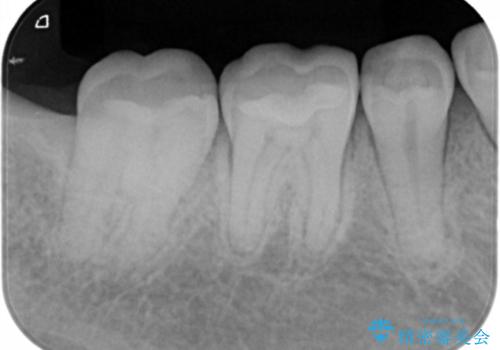

- 右下奥歯の虫歯治療を希望された患者様です。

保険の材料が劣化し、直下で虫歯の存在が確認出来ました。

セラミックを希望されたので形態・切削量を考慮し、セラミックインレーでの治療を計画しました。

虫歯が広く進行していましたが神経には到達していなかったので、予定通りセラミックインレーでの治療を行いました。